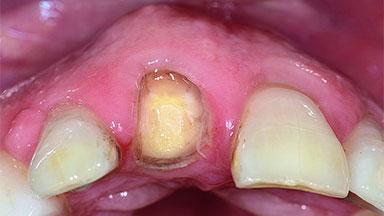

A 49-year-old female patient was referred for implant therapy to replace the upper right central incisor (tooth 11). The tooth had been assessed by an endodontist who diagnosed a vertical fracture of the root. The tooth had a hopeless prognosis and needed to be extracted. The patient was healthy and was not taking any medications. She was allergic to penicillin. The patient had high esthetic demands but her expectations were realistic. The extraoral examination revealed no facial asymmetries. The right temporomandibular joint demonstrated an opening click but was otherwise asymptomatic. The lip line was high with a significant gingival display.

Placement Protocol Early or late implant placement